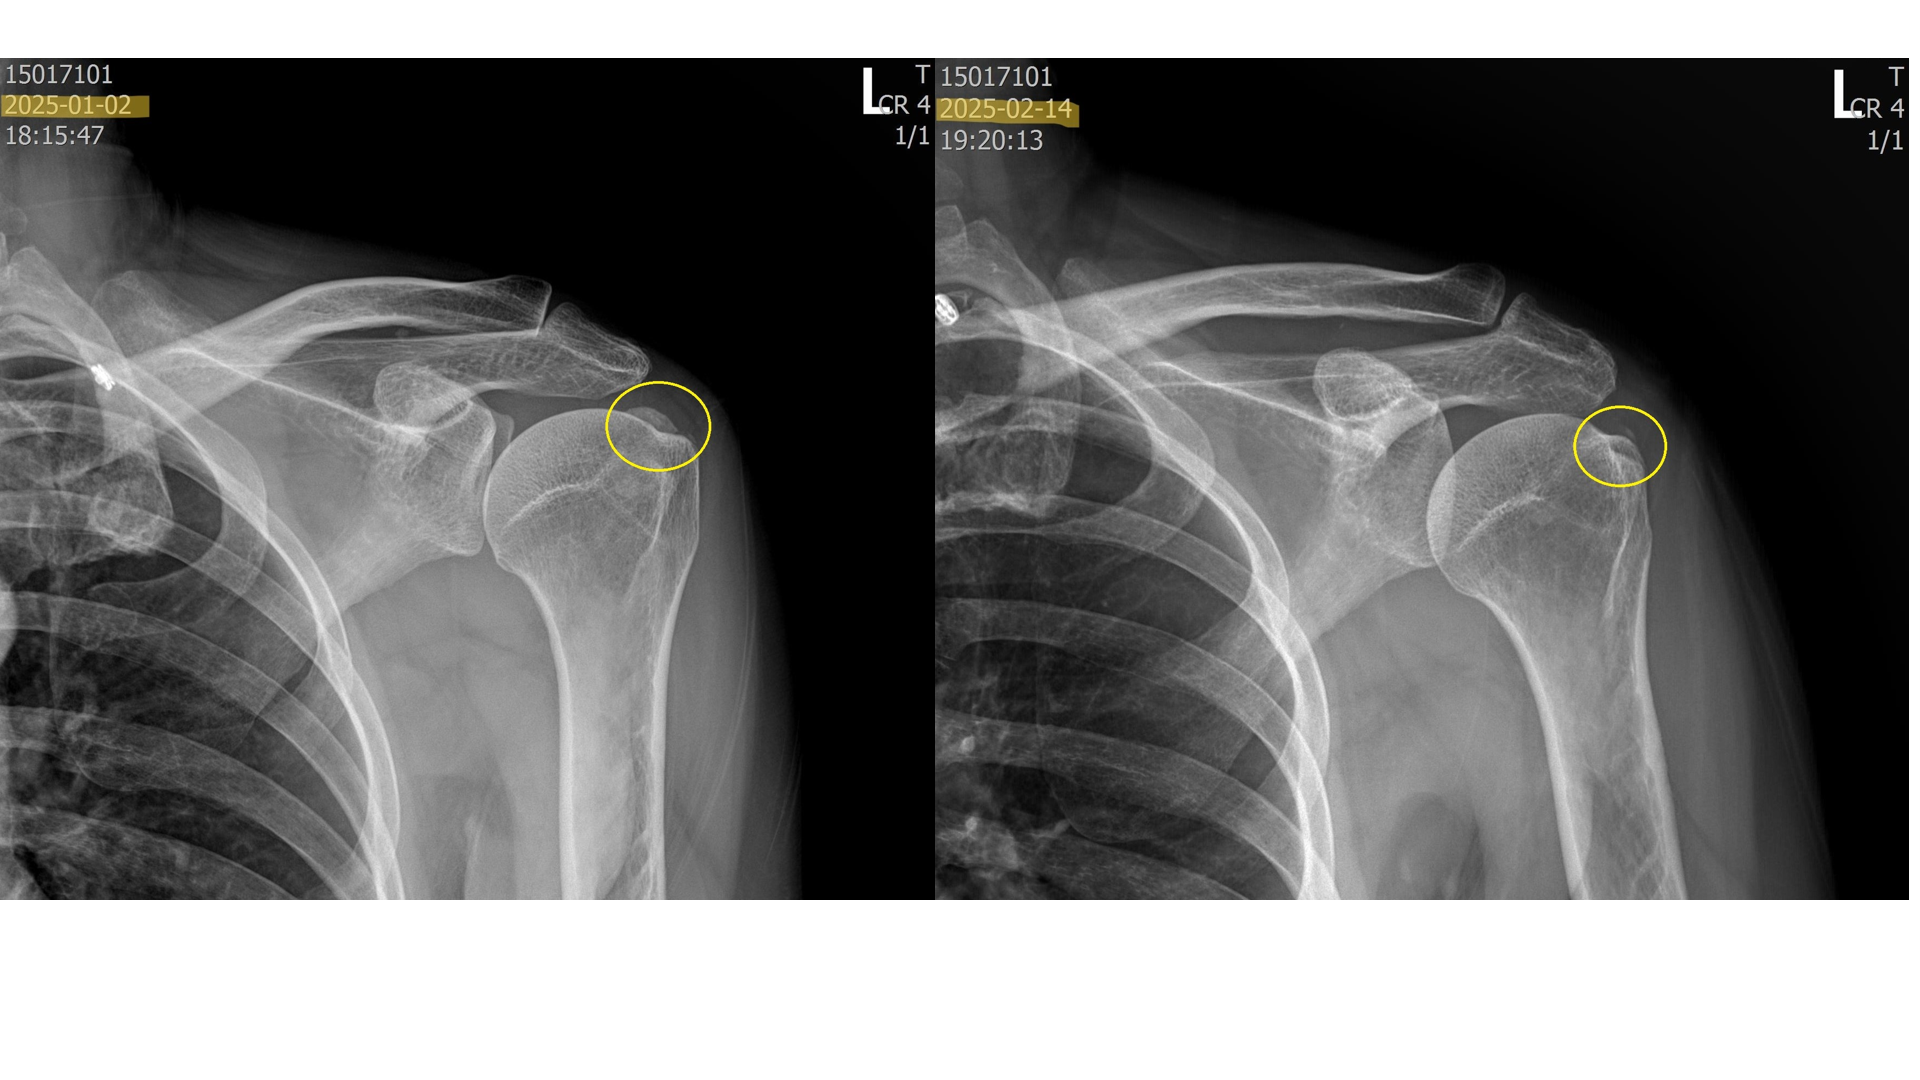

위의 사진은 실제로 내원하여 치료받은 환자들의 x-ray 입니다. 이 환자분들은 약 5회에 걸쳐 섭회흡입술 + 체외충격파시술을 받은 분들입니다. 보시다시피 드라마틱하게 석회가 제거된걸 볼 수 있습니다.